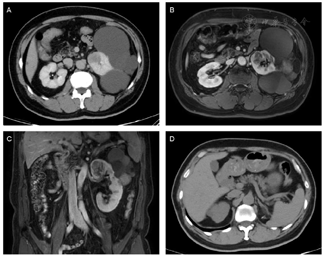

泌尿系CT增强(图1):左肾上部可见团块状稍低密度灶,边缘较清晰,大小约3.4cm,3.1cm,3.5cm,平扫及各期CT值约33HU,47HU,49HU,55HU。双肾实质内可见多个囊性低密度灶,边缘清晰,较大者位于左肾,直径约8.7cm,多期增强扫描病灶未见强化。双肾可见类圆形高密度灶,界清,较大者直径约1.1cm,CT值约74HU,增强扫描未见异常强化。影像学提示左肾上极占位。双肾多发囊肿(Bosniak Ⅰ-ⅡF)。双肾结石。肝多发囊肿。

泌尿系MRI增强(图1):左肾可见多发大小不等囊性灶,双侧肾盏、肾盂、输尿管未见扩张,其内未见异常信号。左肾上部内侧可见结节状T1WI稍低T2WI稍高信号灶,DWI高信号,大小约3.3cm,3.1cm,4.3cm,反相位图像未见明确信号减低,病变延续进入左肾上段肾静脉分支,动态增强扫描可见不均匀轻至中度强化。双肾实质内可见多个囊性T2WI高信号,部分病变T1WI呈高信号及囊壁不均匀增厚,动态增强扫描未见异常强化,较大者位于左肾,直径约8.7cm。影像学提示左肾上极占位,伴左肾上段肾静脉内瘤栓。双肾多发囊肿(Bosniak Ⅰ-ⅡF),肝多发囊肿。

患者术后恢复良好,伤口正常愈合。术后三个月后复查腹部CT平扫示(图1D):左肾切除术后,局部未见明显复发征象。建议患者定期监测,每年行腹部磁共振成像检查。